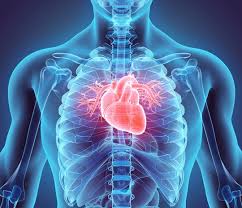

3. 해부학적 표면 및 방향

- 앞 표면(sternocostal surface): 흉골 바로 뒤, 2~5늑간에 위치하며, 주로 우심실이 차지합니다 :contentReference[oaicite:7]{index=7}.

- 아래 표면(diaphragmatic surface): 횡격막 위에 위치하며, 좌심실이 주로 포함됩니다 :contentReference[oaicite:8]{index=8}.

- 폐측면(pulmonary surface): 좌폐와 접촉하는 좌심실 측면입니다 :contentReference[oaicite:9]{index=9}.

- 뒤면(base): 대정맥과 폐정맥이 연결되는 위치로, 심장의 뒷부분을 형성합니다 :contentReference[oaicite:10]{index=10}.

- 첨부(apex): 가슴왼쪽 5늑간선, 중선에서 약 9 cm 떨어진 곳에 위치하며, 좌심실 꼭대기를 형성합니다 :contentReference[oaicite:11]{index=11}.

4. 4개의 심장 방 구조

- 좌우 심방(atria): 위쪽 챔버로, 우심방은 상·하대정맥에서 탈산소혈을, 좌심방은 폐정맥에서 산소 혈을 받습니다 :contentReference[oaicite:12]{index=12}.

- 좌우 심실(ventricles): 아래쪽 챔버로, 우심실은 폐, 좌심실은 전신으로 혈액을 보냅니다 :contentReference[oaicite:13]{index=13}.

- 중격(septum): 좌우 방 사이를 구분하는 두꺼운 벽입니다 :contentReference[oaicite:14]{index=14}.